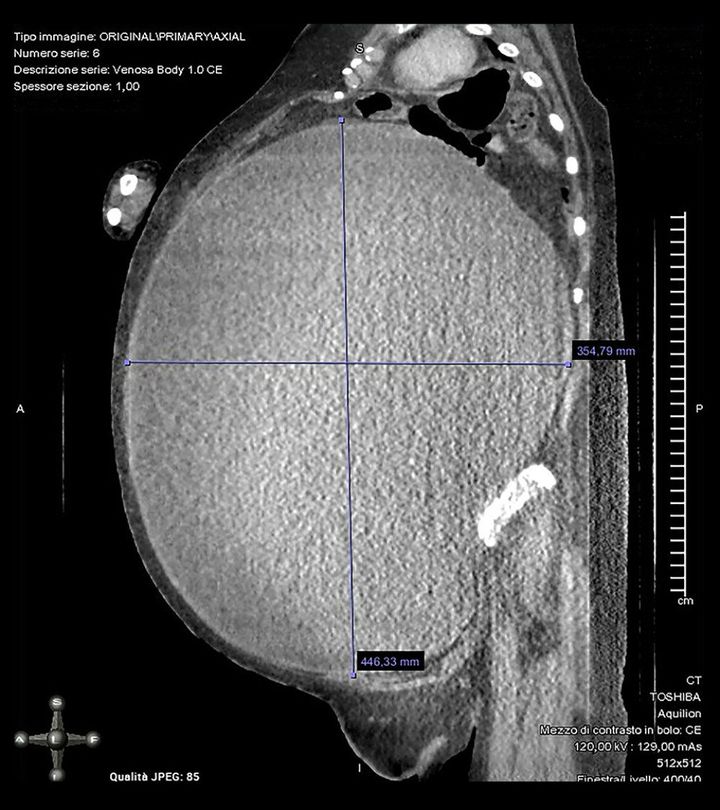

女性の巨大化した腫瘍のスキャン画像

女性の巨大化した腫瘍のスキャン画像 / Credit: Michele Peiretti et al., American Journal of Case Reports(2023)

このイタリア人女性の場合、腫瘍の長さが約40センチ、重さ5キロというサイズにまで成長していました。

ただ女性の腫瘍はこれほど肥大化しているにもかかわらず、破裂の兆候はなく、ホルモンバランスや月経周期にも異常が出ていませんでした。